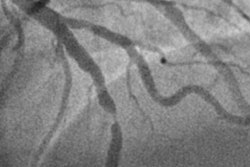

Although invasive coronary angiography with cardiac catheterization has long been the reference standard for diagnosis of obstructive CAD -- and allows for coronary revascularization during the procedure -- it does carry some risk.

"As an invasive examination, cardiac catheterization is associated with rare but serious complications [and] about half of all cardiac catheter examinations in Europe and the U.S. do not result in a CAD finding that requires treatment," the group wrote in a brief about the research.

The investigators compared CT and invasive coronary angiography as diagnostic imaging strategies for 3,667 patients with stable chest pain and intermediate pretest probability of obstructive CAD; the patients were initially referred for ICA at one of 26 European centers.